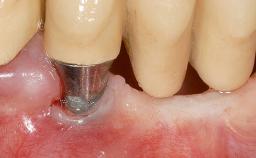

It is sometimes necessary to remove and replace compromised implants. This case is a clear example of the need for multiple steps to achieve an optimal therapeutic result for patients with non-salvageable implants. It illustrates how the lost soft and hard tissues were rebuilt in a sequence that improved the healing of the hard tissues and assured their long-term stability. The 35-year-old healthy patient presented with clinical attachment loss on the proximal and lingual surfaces of the natural dentition. Some gingival recession was present on natural teeth, particularly in the posterior sextants (S1, S3, S4, and S6).

Bone Augmentation Horizontal|Staged|Vertical

Soft Tissue Grafting Staged